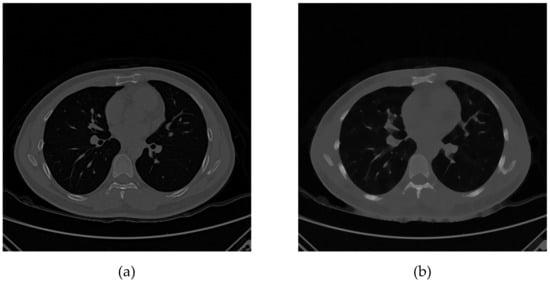

The CT images have interference and noise for various reasons. For this reason, the adaptive median filter was used for noise canceling, and the four neighbors low pass filter was used to enhance the pixels of the suspected airway wall, as shown in Figure 2. The noise was eliminated, and the overall sharpness was reduced.

Figure 2.

Image contrast processing comparison diagram: (a) before processing (b) after processing.